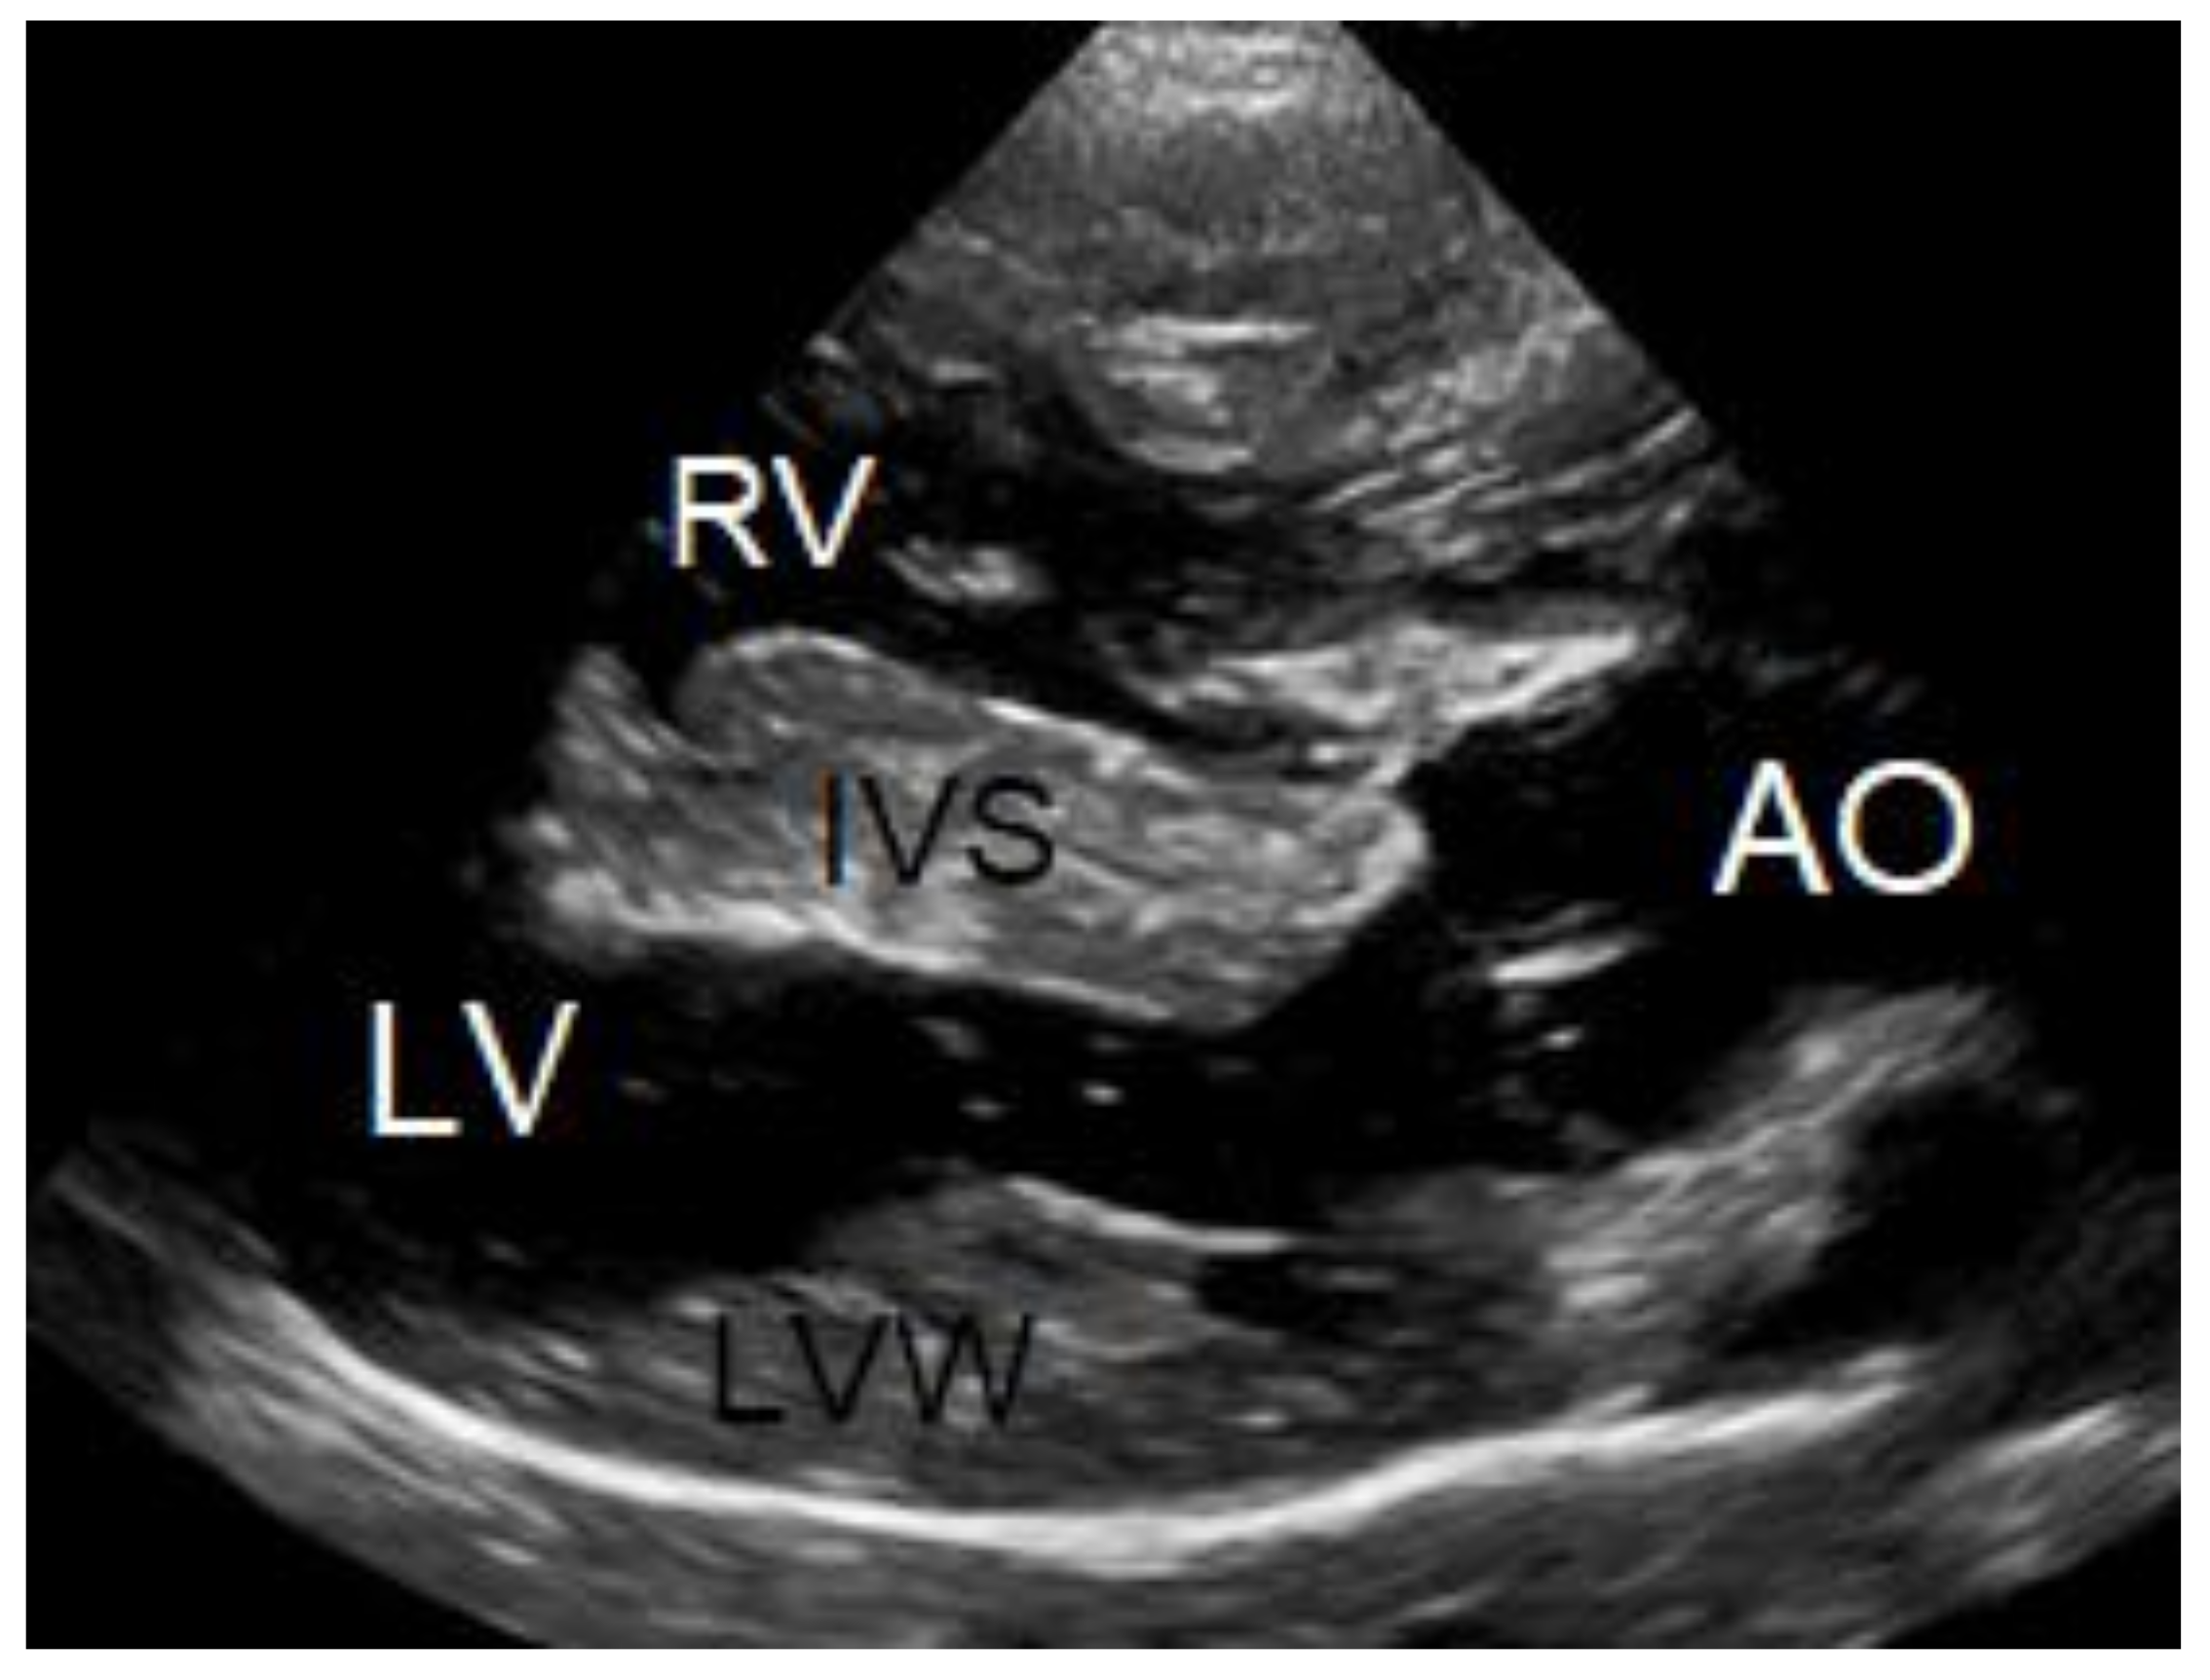

To evaluate the cause of the murmur and the cause of the dyspnea after having obtained thoracic radiographs, an echocardiography was performed in an awake dog without sedation. Echocardiography showed a severe localized right ventricular concentric hypertrophy and a severe obstruction of the right ventricular outflow tract caused by a localized muscular hypertrophy within the right ventricle (Figure 3). The right ventricular lumen at the level of the obstruction measured 1.2 mm, and continuous wave Doppler interrogation revealed a pressure gradient of at least 88 mmHg between the proximal high-pressure and the distal normal-pressure right ventricular compartments. The pulmonary artery and pulmonary valve looked normal, with an annulus diameter of 8 mm and with a normal peak flow velocity of 1.1 m/s (Figure 3). There was no tricuspid valve regurgitation present. The right atrium was subjectively mildly dilated. The left ventricle and left atrium were underfilled (Figure 4). There was a trivial aortic valve regurgitation present, probably secondary to the VSD, since the aortic valve leaflets looked normal. The aortic root diameter was 10 mm. Just underneath the aortic valve, a VSD was seen with a diameter of about 2.5 mm, and color Doppler revealed right-to-left shunting from the high-pressure compartment of the right ventricle to the left ventricle with a pressure gradient of 13 mmHg. A bubble study, i.e., injection of agitated physiologic saline solution intravenously, confirmed the right-to-left shunting at the level of the ventricles (Figure 5). There were no ascites or hepatic venous congestion present.

Figure 4. M-mode echocardiographic images of the right and left ventricles at 10 weeks of age (A) and 3 years of age (B). The most striking difference is the reduced left ventricular chamber (LV) size from normal to too small and the enlargement of the right ventricular chamber (*) caused by a mixed concentric and eccentric hypertrophy. The left ventricular diastolic chamber dimension at 10 weeks of age was 18.7 mm, and this value became 9.9 mm at 3 years of age. Annotations are placed on structures in systole: RVW—right ventricular free wall; IVS—interventricular septum; LVW—left ventricular free wall.